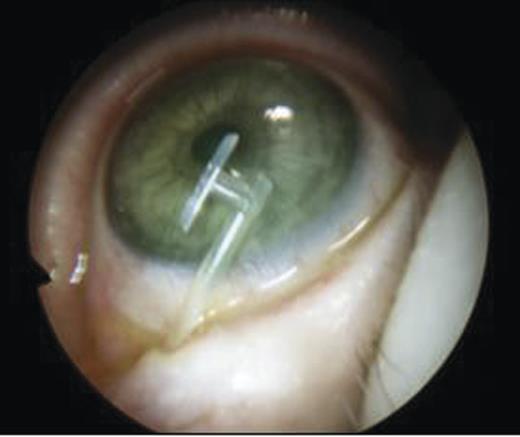

The puncti were probed (Fig. 5) and fluorescein dye instilled with no dye outflow to the left inferior meatus. It was not possible to pass the probe through the upper punctum so a mini-monoka DCR stent was inserted and secured (Figs. 6 and 7). Chloramphenicol eye drops were instilled.